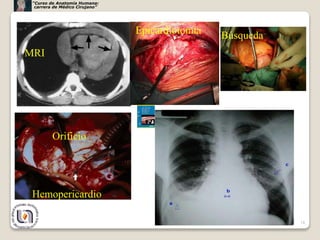

MRI hemopericardio

Rx Hemopericardio

Epicardiotomía

MRI

Búsqueda

Orificio

Hemopericardio